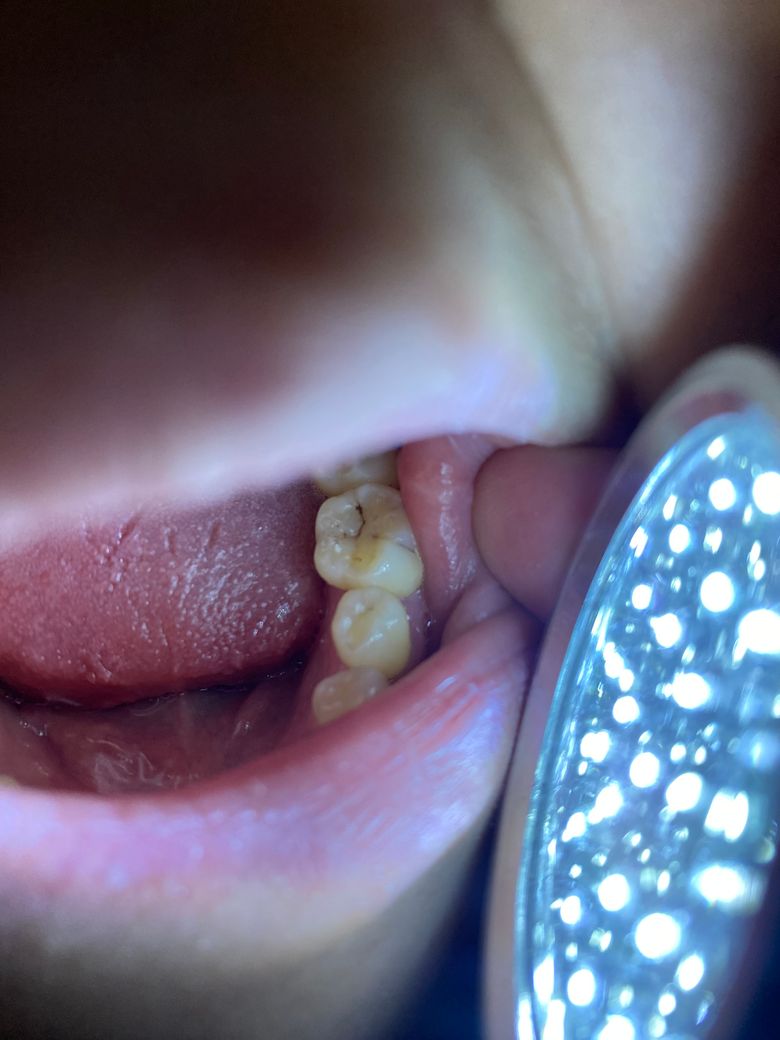

충치상태는 이랬습니다

-치료전 충치사진